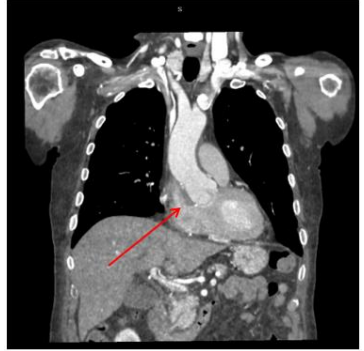

Echocardiography revealed a dilated aortic root (50 mm), preserved myocardial contractility, and an ejection fraction of 55%. A significant leak from the aorta into the right atrium was identified (Figure. 1). Computed tomography confirmed contrast leakage from the noncoronary sinus into the right atrium (Figure. 2). An anatomical anomaly was also observed, with the right coronary artery originating just above the ostium of the left coronary artery. Coronary angiography showed no significant stenoses.

Figure 2: Contrast-enhanced computed tomography scan performed before surgery. The arrow indicates the site of the aneurysm rupture into the right atrium.